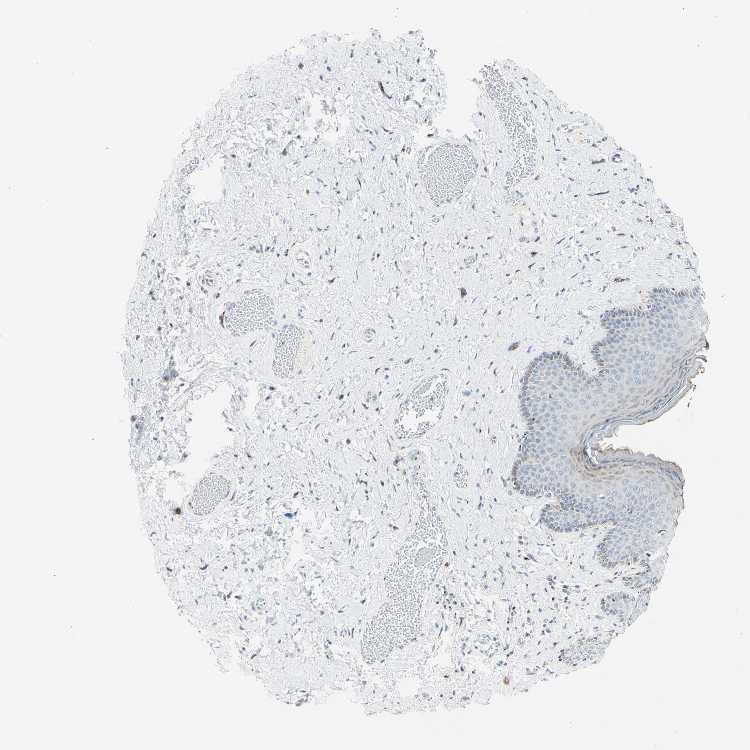

SKIN 1 - Antibody stainingi

Antibody staining in the annotated cell types in the current human tissue is reported as not detected, low, medium, or high, based on conventional immunohistochemistry profiling in selected tissues. This score is based on the combination of the staining intensity and fraction of stained cells.

Each image is clickable and will lead to virtual microscopy that enables deeper exploration of all samples and also displays staining intensity scores, fraction scores and subcellular localization as well as patient and tissue information for each sample.

Antibody HPA011222

Langerhans Not detected

Fibroblasts High

Keratinocytes Medium

Melanocytes Medium